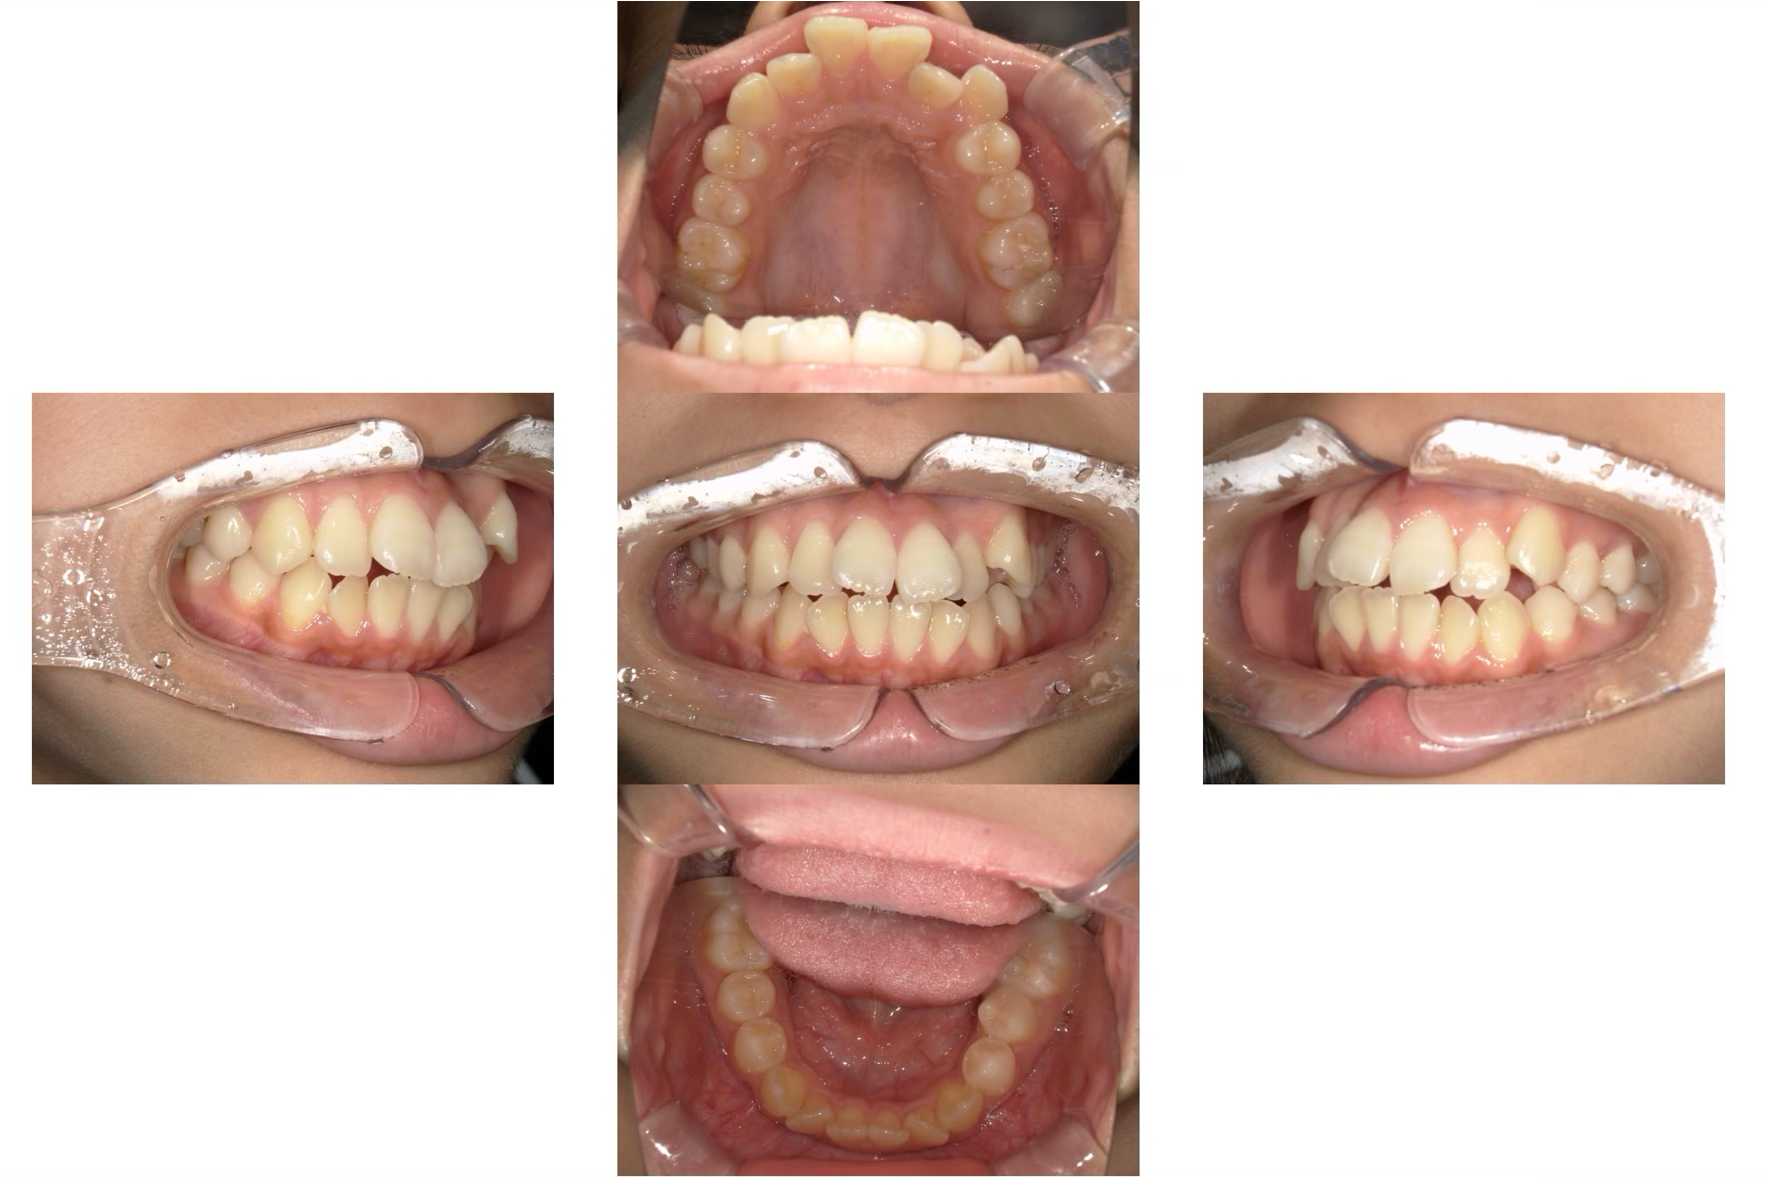

治療前

治療後

| 年齢 | 52歳 |

| 主訴 | 前歯でものが噛みきることが出来ない。 |

| 治療期間 | 約2年 |

| 治療費 | マウスピース型矯正装置 税込990,000円 |

| 概要 | 前歯でものを噛みきることが出来ず、年を取るにつれ奥歯が悪くなってきた気がするとのことでした。 ご相談させていただき、歯を抜かずにマウスピース矯正にて矯正治療を行わせていただきました。 |

治療期間は2年かかりましたが、見た目だけでなく前歯でしっかりものを噛めるようになり大変満足していただけました。